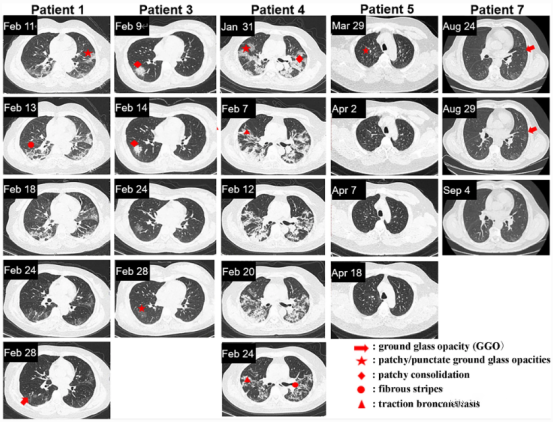

其他五名患者的CT图像如下图所示,能发现从一开始就接受外泌体治疗的人(患者5、7)和抗病毒治疗一段时间后再接受外泌体治疗的人(患者1、3、4)在肺部病变完全吸收的时间之间存在显著差异。

▲患者1、3、4、5和7的胸部CT图像

该项试验的结果表明,在参与受试的COVID-19患者中,雾化吸入间充质干细胞衍生的外泌体是可行的,并且耐受性良好,没有预先指定的不良事件的证据。参与者的肺部炎性症状,得到了不同程度的改善。